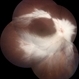

- Myelinated Nerve Fibres, Medullated Nerve fibres, MNF

Fundus camera

Zeiss Clarus 700 - Description

- Fundus photograph of 32-year-old male with myelinated nerve fibre as incidental finding